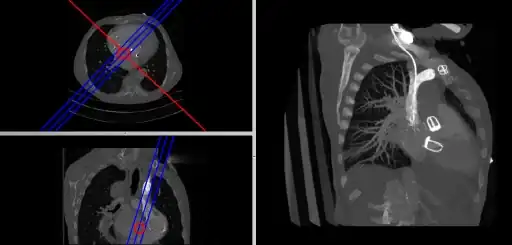

- Oblique Reconstruction

- Oblique MPRs are possible by defining angled planes through the voxel data , as illustrated in the following figure:

- Here the plane can be defined in, say, the axial images (red line, top left) and a maximum intensity projection (the limits used are highlighted by the blue lines), for example, can be displayed for the reconstructed plane (right). This technique is useful when attempting to generate perspectives in cases where the visualization of three-dimensional structures is complicated by overlapping anatomical detail.